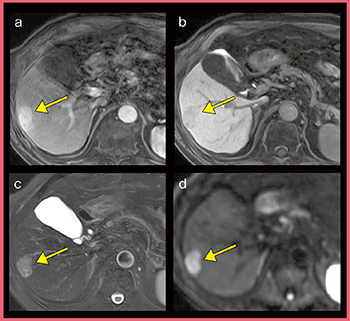

●EOB造影MRIにおける有用性

肝腫瘍診断におけるEOB造影MRIでは,より確実な診断のために,すべてのシーケンスを詳細に評価する必要があり,どのシーケンスでも良好な画像を撮像できることが重要となる。

図4の症例は,動脈相(a)で淡く染まる病変が肝細胞造影相(b)では淡い低信号として描出されており,これらの画像のみでは偽病変の可能性も考えられる。しかしながら,同病変はT2強調画像(図4 c)で明瞭な高信号,DWI(d)で拡散制限が認められたことから,偽病変ではなく,EOBを取り込むタイプの原発性肝細胞がんであると考えられた。本症例は,手術にて肝細胞がんであることが確認されており,すべてのシーケンスにおいて良好な画像が撮像できるTRILLIUM OVALの有用性を実感した症例である。

図4 原発性肝細胞がん症例(偽病変との鑑別)

a:arterial phase b:hepatobiliary phase

c:T2強調画像 d:DWI(b=1000s/mm2)